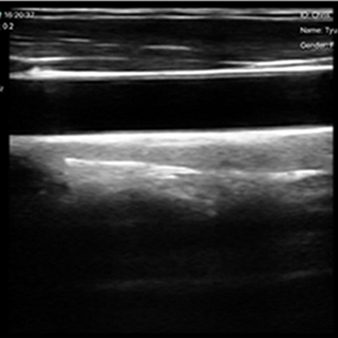

El escáner de ultrasonido portátil de doble sonda es una solución avanzada diseñada para ofrecer máxima versatilidad clínica en un solo dispositivo. Gracias a su tecnología integrada, combina tres modos de escaneo —convexo, lineal y phased array— permitiendo evaluar estructuras profundas, tejidos superficiales y realizar estudios cardíacos con alta precisión. Esta integración reduce significativamente los costos al reemplazar la necesidad de adquirir múltiples sondas por separado.

| Tipo de sonda | Matriz convexa + Matriz lineal |

| Ángulo/longitud de escaneo | Convexo 60, Lineal 40 mm |

| Frecuencia | Sonda convexa de 3,5/5,0 MHz, sonda lineal de 7,5/10 MHz |

| Profundidad de la pantalla | Convexo 90 ~ 305 mm, Lineal 20 ~ 100 mm |